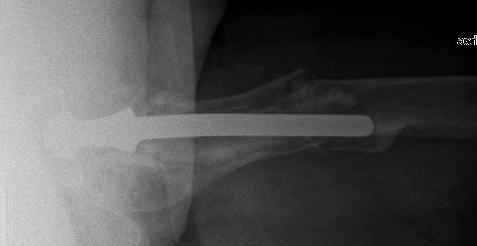

You transformed a cemented hip prosthesis to a cementless revision hip prosthesis with a little approach.

* your nail has a point of minus resistance at the tip of femural stem and at the fulcrum of the fracture; by the time could it break?

* by the time stem and nail could reciprocally move?

* distal fixation of the nail is based near only on two screws : are they sufficient to secure a good stability before fracture consolidation?

* materials of the stem and nail (I think Iron steel in both); if they should be different (and many hip prosthesis are made by an alloy that is not the same of the nails) we could see electrolytic phenomena